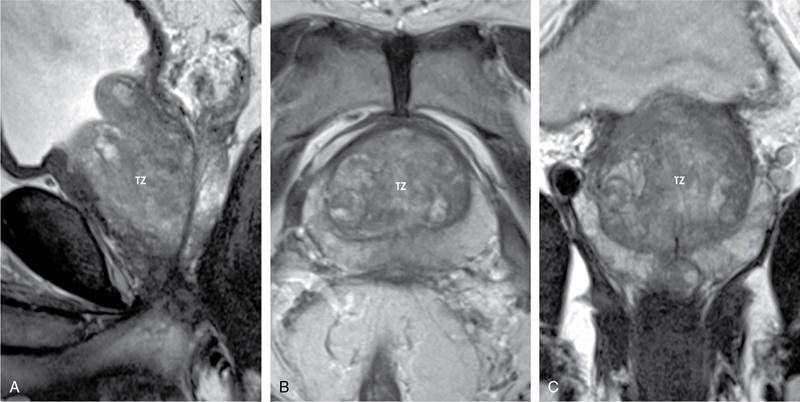

Karthik Ganesan, Disha Lokhandwala, Ujjwal Bhure, Jay Mehta Morphogenesis of the male genitourinary system is governed by the coherent interaction of three units, namely the Wolffian duct, urogenital sinus and foetal gonads. The Wolffian ducts are the embryonic precursors of the male internal genitalia, arising in the anterior intermediate mesoderm at 4 weeks of gestation. They elongate as a cord of cells that caudally extend to the urogenital sinus. Between 5 and 8 weeks of gestation, the urorectal septum divides the cloaca into a ventral compartment, which forms the urogenital sinus, and a dorsal compartment, which forms the rectum. The gonads form as epithelial thickenings on the ventromedial surface of the mesonephros and produce testosterone at 8 weeks of gestation, reaching a peak at 10–15 weeks. Under the effect of testosterone produced by the foetal testis, the prostate anlage forms at the tenth week of gestation. Precursor of the anlage begins with proliferation of solid epithelial buds from the epithelium of the urogenital septum into the adjoining mesenchyme in response to interaction of 5α-dihydrotestosterone with mesenchymal androgen receptors. As growth progresses, solid cords of epithelial cells are formed, growing into the mesenchyme in a specific three-dimensional arrangement (establishes the lobar divisions of the prostate gland). These solid cords develop a central lumen at birth and are lined by a layer of flat basal epithelium and a luminal layer of tall columnar secretory epithelium. Mesenchymal component forms the stroma, which has a large proportion of smooth muscle. Postnatally, the epithelial cords continue to arborize till puberty without any change in volume or glandular architecture. Although the foetal prostate has been described to have a histologically distinct peripheral zone (PZ) as early as 12 weeks of gestation, the mature zonal anatomy develops in concordance with the androgen surge at puberty. The most commonly utilized ultrasonographic technique for the evaluation of the prostate is via a suprapubic approach. The abdominal transducers used in this approach are relatively low frequency and while it offers the advantage of greater depth of penetration without intracavitary probe insertion; however, it does not depict the zonal anatomy and its chief application lies in volume estimation. Hence, transrectal ultrasonography (TRUS) completely outweighs the transabdominal approach in terms of depicting zonal anatomy, visualizing and localizing small lesions, demonstrating vascularity and performing biopsies. TRUS is performed using high frequency transducers (5–7.5 MHz) to optimize soft tissue resolution. An enema is administered 1 h prior to the examination to clear the field of insonation. Patient is positioned in left lateral decubitus, with knees bent toward the chest and ideally a digital rectal examination (DRE) is conducted prior to probe insertion. The transducer is first draped with a sterile barrier and lubricated, After insertion, the barrier is filled with 40–50 cc of water, making sure that no air enters. On completion, water is aspirated and the probe is withdrawn. The gland is initially scanned in the axial plane from the base to the apex, beginning at the level of the seminal vesicles, and the probe is gradually withdrawn to view the entire glandular parenchyma in axial sections up to its caudal aspect. This approach allows a cursory evaluation of glandular symmetry as both halves of the prostate can be evaluated simultaneously. Subsequently, sagittal views are acquired by rotating the probe across the transverse span of the gland, demonstrating the seminal vesicles, midline gland (visualizing both the apex and the base), with sequential scanning up to the contralateral margin of the gland. Sonographically, the prostatic capsule is seen as a smooth well-delineated, hyperechoic structure. With the newer ultrasound systems, the zonal anatomy can be delineated by TRUS; PZ appears echogenic relative to the central zone (CZ) and the transition zone (TZ), which are hypoechoic in juxtaposition (Fig. 11.12.1). Anterolaterally, the preprostatic venous plexuses are seen as anechoic tubular structures with intervening echogenic preprostatic fatty tissue. Glandular volume is estimated using an ellipsoid formula by obtaining the maximum anteroposterior, superoinferior and transverse dimensions and multiplying their product by π/6. Colour Doppler imaging is utilized to illustrate vascularity, as majority of the normal prostatic tissue (excluding the neurovascular bundles [NVBs] and pericapsular and periurethral regions) has symmetrical but sparse flow and an increased microvessel density raises the suspicion of prostatic carcinoma. However, the appearances of prostatic carcinoma can be variable on colour Doppler imaging, ranging from focal increase in vascularity around a nodule to an asymmetric increase in size and number of vessels on the affected side and conventional Doppler has found to elevate specificity by about 5%–10%. Additionally, Doppler imaging has also demonstrated some utility in distinguishing fibrotic tissue from local recurrence. However, vessels supplying cancerous tissue are of the order of 10–50 μm, which is well below the 1-mm resolution limit of conventional Doppler techniques. Contrast-enhanced colour Doppler imaging overcomes this limitation and facilitates imaging of microvessels, using intravenously administered microbubbles (less than 10 μm diameter) of an inert gas (sulphur hexafluoride) with a lipid or galactose shell, allowing quantification of blood flow in the cancerous microvessels. Additionally, these microbubbles act as vascular tracers and by monitoring the passage of a bolus injection through the tissue of interest, time–intensity curves are created. This permits the formulation of functional indices, including bolus arrival time, time to peak intensity, area under the curve and wash-in/wash-out curves. These indices can further extrapolate functional images, on a pixel-by-pixel basis, overlaid on grey-scale images. Quantitative methods to demonstrate perfusion are based on the destruction of microbubbles by high-power ultrasound pulses, and then observing the rate of microbubble replenishment in the field of interest to calculate flow rate. Halpern et al. utilized contrast-enhanced ultrasound and intermittent harmonic imaging with power Doppler, and exhibited an increment in sensitivity from 38% to 65% with a specificity of 80% in prostate cancer detection. Cadence contrast pulse sequencing (CPS) is a low-power multipulse imaging technique utilizing pulses with variable amplitudes and phases followed by a summation of the resulting echoes, permitting tissue suppression, allowing detection of even a small amount of contrast agents retained in the tissues. Real time elastosonography evaluates and quantifies tissue stiffness (Young’s modulus) by measuring strain under an applied stress (transducer compression) and maps areas of variable stiffness in colour-coded and grey-scale images simultaneously and shows potential in improving prostatic carcinoma detection. In a study comparing elastography and T2-weighted (T2-w) endorectal magnetic resonance imaging (MRI), similar sensitivity rates and negative predictive values (NPVs) were attained in the detection of prostatic carcinoma. Prostate gland is an inverted cone-shaped subperitoneal retropubic gland, with its base located rostrally and apex located caudally. The base is attached to the bladder neck and the apex sits on the urogenital diaphragm and abuts the medial surface of the levator ani muscles, namely the pubourethralis portion, which is separated from the inferolateral surfaces of the gland on either side by the prostatic venous plexus. Normal prostate gland measures approximately 4 × 3 × 3 cm, 15–20 g in weight, with a median volume of 11.5 mL (range, 1.6–20.6) in patients between 21 and 25 years and a median volume of 39.6 mL (range, 13–169.8) in patients between 38 and 83 years. The first comprehensive publication describing the anatomical subdivision of the prostate gland was in 1912 by Lowsley, based entirely on the embryonic glandular morphology at a series of gestational age groups. The budding prostatic ducts were seen to proliferate in five distinct clusters from the primitive urogenital sinus, which formed the basis of its lobar subdivision. It was divided into a ventral lobe (anterior to the urethra), two lateral lobes (lateral to the ejaculatory ducts), a posterior lobe (between the ejaculatory ducts) and a middle lobe (above the ejaculatory ducts). This classification had several shortcomings, the foremost being inclusion of only the embryonic prostate during its conception. Frank highlighted these aspects in 1953 and stated that no definite lobar boundaries exist in the adult prostate and further criticized the exclusion of periurethral glands (inner gland), identifying them as the sole site of origin of benign prostatic hyperplasia (BPH). The chief drawback of all research prior to 1968 was the lack of a concrete histological basis to support the seemingly arbitrary subdivision. McNeal was the first to ascertain histological heterogeneity within the glandular tissue and used it as the basis of his well-acclaimed prostatic zonal classification. The zonal anatomy of the prostate gland conceived by McNeal divided the gland into four distinct zones, namely the TZ, PZ, anterior fibromuscular zone (AFMZ) and the CZ (Fig. 11.12.2). McNeal used the plane of the distal urethra to describe the zonal relationships and divide the gland broadly into three parts, namely the base, midgland and the apex (Fig. 11.12.3). The improved understanding of the prostate anatomy coincided with the development of MRI in the late 1980s, which could depict the zonal anatomy, unlike ultrasonography (USG) or computed tomography (CT). Patterns of ductal growth and radiation from the prostatic urethra form the basis of the zonal anatomy of the gland. Ducts arising from the proximal urethral segment grow towards the urinary bladder. Tiny ducts which are confined by the preprostatic sphincter form the small periurethral gland, whereas ducts which develop distal to the lower border of the preprostatic sphincter extend laterally and then anteromedially to form the TZ. Ducts arising from the verumontanum in the vicinity of the ejaculatory duct orifices and are directed towards the base along the course of the ejaculatory ducts form the CZ, whereas ducts which arise from the lateral recess of the posterior urethral wall of the verumontanum and distal urethra radiate laterally to form the PZ and rostrally posterior to the CZ at the base of the gland. PZ is the dominant glandular component of the prostate gland comprising approximately 70% of the glandular tissue. On T2-w images, the normal PZ has a high T2 signal intensity (SI), owing to the abundant ductal and acinar elements with sparsely interwoven smooth muscle, and can broadly divided into three sections as per the sector map in Prostate Imaging Reporting and Data System Version 2.1 (PI-RADS v2.1), namely posterior medial, posterior lateral and anterior sections (Fig. 11.12.4). At the apex, the anterior sections have a horn-like morphology, curving anteromedially, to nearly encircle the urethra and abut the AFMZ. At the midgland level, the PZ comprises the posterior, both lateral and the anterolateral parts of the gland. At the base, the PZ is located posterior and superior to the CZ and TZ. CZ is an ovoid-shaped structure at the base of the gland, comprising approximately 25% of the glandular tissue, with its apex located at the verumontanum, surrounding the ejaculatory ducts. Beyond age 35, volume of the CZ starts to gradually diminish, as well as the CZ is compressed by the enlarged TZ. In the initial MR studies of prostate, the CZ could not be easily delineated from the TZ. Vargas et al. demonstrated in a population with a mean age of 60 years undergoing MR for prostate cancer assessment, the CZ was visible in 81%–84% of patients. Hansford et al. identified the CZ in 92%–93% of patients on T2-w images and 78%–88% of patients on apparent diffusion coefficient (ADC) maps. Histologically, substantial differences exist between the CZ and PZ, which reflect in the differential appearance on T2-w imaging. These differences are probably attributable to the differential origin, as the CZ is derived from the Wolffian duct, and the PZ and TZ are derived from the urogenital sinus. In the CZ, the acini appear larger and more irregular, with numerous epithelial covered ridges or septa project from the walls of the acini into the lumen, forming a characteristic Roman bridge architecture and intraglandular lacuna, with a prominent basal layer, crowded epithelial cells with granular eosinophilic cytoplasm, decreased luminal fluid and compact stroma. PI-RADS v2 has discouraged the use of the term central gland, as it is not reflective of zonal anatomy or reported on pathologic specimens. CZ demonstrates homogeneously low signal on the T2-w images and ADC maps and can, therefore, mimic prostate cancers. CZ is best identified on the coronal plane T2-w images paralleling the plane of the distal urethra, and appears as a symmetric paramedic paired structures surrounding the ejaculatory ducts from the base of the gland to the verumontanum (Fig. 11.12.5). TZ comprises approximately 5% of the glandular tissue of the prostate. On T2-w images, the TZ normally appears as a homogeneously hypointense structure surrounding the proximal urethra at the base and the midgland level; however, it can also demonstrate inconsistent SI, depending on the relative proportion of glandular and stromal elements (Fig. 11.12.6). Glandular hyperplasia produces higher SI (dominance of acinar elements and secretions), while stromal hyperplasia exhibits lower SI (dominance of muscular and fibrous elements). The TZ is easily demarcated from the PZ by a thick homogeneously low T2 signal surgical capsule, which becomes pronounced in BPH. With increasing age, the TZ demonstrates variegated signal on the T2-w images and ADC maps, due to differential growth of the stromal and glandular elements. AFMZ is a nonglandular muscular tissue that drapes the anterior surface of the gland, superiorly blending into the smooth muscles of the bladder neck and inferiorly extending to the prostatic urethra at the glandular apex. AFMZ is comprised of smooth muscles, which blends with the smooth muscle fibres surrounding the urethra, and rostrally merges with the bladder neck and preprostatic sphincter. High smooth muscle content of the AFMZ is responsible for the MR signature, where in it appears markedly hypointense on the T2-w images and ADC maps, and hypoenhances on the multiphase contrast series (Fig. 11.12.7). With the advancing age, temporal reduction in the size of the AFMZ is noted due to the compressive effects of the BPH. Capsule surrounds the prostate gland, anteriorly merging with the AFMZ anteriorly. Two discrete defects are identified in the prostate capsule, at the base of gland where the ejaculatory ducts enter the prostate and at the apex where in the stroma blends with the sphincter. The capsule is perforated along the anterolateral aspect by multiple vessels and nerves. The capsule appears as a thin dark rim surrounding the gland on the T2-w images and may reveal delayed enhancement on the postcontrast images (Fig. 11.12.8). Primary goal of radical prostatectomy (RP) is to achieve oncologic efficacy, both in terms of short-term and long-term clinical outcomes. However, as the majority of prostate cancers have an indolent clinical course, preservation of function in terms of continence and potency is equally important, and the key to this is a keen understanding of the fascial anatomy and neuroanatomy of the prostate gland. Fascial anatomy of the prostate gland is anatomically complex and poorly understood, and a thorough understanding of the interfacial planes is crucial to avoid mechanical or thermal injury to the NVBs. Periprostatic fascia comprises of a condensation of layers of connective tissue that encapsulate the gland and suspend it from anterior pelvic wall via puboprostatic ligaments. Laterally, the visceral and parietal endopelvic fascial layers fuse to form the fascial tendinous arch. Periprostatic fascia covers the prostate gland and capsule, comprises of two fascial layers, including an inner layer (prostatic fascia) and an outer layer (levator ani fascia), with thin interfascial planes separating these fascia from one another and the prostate capsule. Posteriorly, a continuous fascial layer known as Denonvilliers’ fascia covers the prostate and seminal vesicles. Distribution of periprostatic nerves is highly variable, with growing evidence of nerves both along the dorsolateral and ventrolateral surfaces of the prostate gland. Most of the periprostatic nerves are found posterolaterally; however, a significant portion of the nerves are located ventrally as seen by Eichelberg et al. (21.5%–28.5%) and Lee et al. (19.9%–22.8%). Although anatomic studies have confirmed the presence of ventrolateral periprostatic nerves, the exact clinical importance and functionality of these nerve fibres has not been proven. The cavernous nerves are situated posterolaterally and are the basis of nerve-sparing RP procedure proposed by Walsh and Donker. Unlike the initial theory of Walsh and Donker, few papers have proposed that the nerves are diffusely scattered along the surface of the gland in the form of a curtain or spray-like arrangement without clear bundle formation. Kourambas et al. assessed the precise relationship of the NVBs and cavernous nerves to Denonvilliers’ fascia and proposed that the nerves were not restricted posterolaterally, but were rather diffusely scattered within the fascia extending up to the midline (Lunacek et al., Takenaka et al.). On the basis of more diffuse arrangement of the periprostatic nerves, surgical techniques have been modified, resulting in a more anterior dissection called the ‘curtain dissection technique’ or alternatively a ‘superveil’ technique to preserve the NVBs within the lateral prostatic fascia. The NVB lies within areolar connective tissue surrounding the gland, which separates the capsule from the periprostatic fascia and provides a plane of dissection during nerve-sparing prostatectomy. Prostate gland is supplied and drained by periprostatic vessels, which also supply and drain the penis. Arterial supply of the gland is highly variable and is typically from branches of the internal pudendal artery, which course inferior to the gland prior to supplying the penile cavernosal tissue. Off late, these vessels have gained prominence in radiation-induced erectile dysfunction (ED) (potential vasculopathy), which have led to the development of newer vessel-sparing radiotherapy techniques. Further, with the advent of prostate arterial embolization in benign prostatic hypertrophy (BPH), the vascular supply of the gland is becoming increasingly vital to understand. Gland drains into the obturator, internal iliac, external iliac, common iliac and presacral lymph nodes. Dorsal venous complex is identified immediately ventral to the gland and also drains the penis. Periprostatic nodes are uncommon, are usually discovered near the base of the gland, and are only occasionally seen on MRI. Urethra is the principal anatomic reference point in the prostate gland. Urethra can be divided into a proximal segment and a distal segment, the point of differentiation being located at the verumontanum wherein the urethra makes an approximately 35-degree angulation. The angulation is highly variable and is further affected by the growth of the TZ. On MRI, the distal segment is more conspicuous vis-à-vis the proximal segment and appears a hyperintense core surrounded by a low signal rim on T2-w images. Preprostatic sphincter encases the proximal urethra from the base of the gland to the base of the verumontanum and merges with the AFMZ anteriorly. Verumontanum appears hyperintense on the T2-w images, lies within the distal urethral segment, beyond which the distal urethral segment is partially encircled by striated muscles which blend with the external sphincter beyond the apex of the gland. External sphincter is located distal to the apex is incomplete posteriorly and is anchored into the PZ and surrounds the membranous urethra. Damage to the external sphincter during RP or transurethral resection of the prostate (TURP) may lead to urinary incontinence. Seminal vesicles are paired structures identified posterosuperior to the base of the prostate gland, which appear as convoluted fluid-filled structures. Due to the high fluid content within the normal seminal vesicles, these structures appear as paired structures with intermediate signal walls surrounding a hyperintense core on T2-w images (Fig. 11.12.9). Vas deferens are paired structures located rostral to the base of the gland and anteromedial to the seminal vesicles and appear as cord-like structures with variable signal on the T2-w images. Duct of the seminal vesicle and vas deferens unite in the posterior aspect of the base of the gland to form the ejaculatory duct, which courses caudally to the verumontanum along the plane of the distal urethra, and drain into the orifices in the midconvexity of the verumontanum. Prostate-specific antigen (PSA) is a serine protease, secreted by epithelial cells of the prostate gland and has been found in normal, benign and malignant prostatic tissues. Traces of PSA have also been isolated from endometrial tissue, breast tissue, adrenal neoplasms and renal cell carcinomas; however, for all clinical purposes, PSA is considered as an organ-specific biomarker. Papsidero first demonstrated and quantified serum PSA, which steered the epoch of prostate cancer screening and early detection of prostatic carcinoma. Subsequent studies showed that PSA screening often led to overdiagnosis of low-grade prostate cancers, with no survival difference between the PSA screened and nonscreened groups. Additionally, PSA levels were found to be elevated in a spectrum of prostatic pathologies apart from carcinoma, including prostatitis and benign hyperplasia. The likelihood of overdiagnosis coupled with the lack of specificity set grounds for the longstanding PSA controversy. Did the benefits of screening outweigh the risks of overtreatment? To elevate the specificity of serum PSA testing, a plethora of indices were devised, including free PSA and total PSA, free-to-total PSA (f/t PSA) ratio, age-specific PSA, PSA velocity (PSA-V) and PSA density (PSAD). Serum PSA exists in three forms; the major form (approximately 75%) is bound to alpha-1-antichymotrypsin, followed by free PSA (constituting 5%–50% of serum PSA). The third form (PSA bound to alpha-2-macroglobulin) is not clinically relevant and cannot be detected by any commercial test. A study by Stenman et al. established that a higher proportion of bound PSA and hence a lower ratio of f/t PSA is associated with prostate cancer. Conversely, free PSA can be utilized during follow-up for men with an initial negative biopsy result, wherein declining free PSA with a persistently elevated total PSA would raise suspicion of a neoplastic aetiology. As per the ACS guidelines (Table 11.12.1) for early detection of prostate cancer, men with a 10-year life expectancy or higher should have the opportunity to make an informed (regarding benefits, risks and uncertainties associated with PSA screening) decision for serum PSA testing, with or without DRE. For those who choose to undergo PSA screening, subsequent screening interval is determined on the basis of baseline PSA value. For values below 2.5 ng/mL, screening interval can be extended to 2 years and for PSA between 2.5 ng/mL and 4 ng/mL, an individualized approach is adopted following risk assessment to recommend either further referral or screening on a yearly basis. A PSA level of 4 ng/mL or higher warrants referral for further evaluation or biopsy, for men at average risk for prostate cancer. Although age-specific PSA (Table 11.12.2) is not a component of the ACS guidelines, it is considered as a beneficial parameter in determining the need for biopsy. As there is an expected rise in PSA values with age, setting a lower cut-off value for younger men would increase the sensitivity of detecting organ confined cancers and a higher value in older men would increase specificity. aThere is no proven rationale for using a single PSA-V threshold value. PSA screening guidelines for treated localized prostate cancers are variable and the definition of biochemical (PSA) recurrence remains debatable. Due to this inconsistency, the Prostate Cancer Guidelines Update Panel recommended a standard definition for biochemical recurrence (BCR) after RP and set a cut-off serum PSA (acquired between 6 weeks and 3 months of surgery) of 0.2 ng/mL or greater, along with a second confirmatory PSA. While there is a significant fall in PSA values after RP and a single raised PSA is sufficient to raise suspicion of recurrence, postradiotherapy recurrence requires a rising trend rather than a single cut-off value. The ASTRO Consensus Panel defined postradiotherapy prostate cancer recurrence as three consecutive raises in PSA values after a baseline has been reached. A hiatus in this definition was that no specific time interval between consecutive increases in PSA was determined. In addition to its utility as a screening tool, PSA is also a good prognosticator when used in conjunction with biopsy Gleason score and clinical T-stage, and several pretreatment prostate cancer risk stratification systems are based on these indices. D’Amico et al. proposed a three-group risk stratification system in 1998, which categorized nonmetastatic (M0) carcinomas as low risk, intermediate risk and high risk. Low-risk prostate cancer was defined as 1992 AJCC T1/T2a, PSA ≤10 ng/mL and Gleason score ≤6. Intermediate-risk prostate cancer was defined as 1992 AJCC T2b, and/or PSA 10–20 ng/mL and/or Gleason 7 disease. High-risk disease included any one of the following: 1992 AJCC ≥T2c, PSA >20 ng/mL or Gleason 8–10 disease. In 2001, the GUROC published the results of a consensus meeting which categorized the groups as follows: low risk – 1997 AJCC T1–T2a, PSA ≤10 ng/mL and Gleason ≤6; intermediate risk – 1997 AJCC T1–T2, PSA ≤20 ng/mL and Gleason ≤7 not otherwise low risk and high risk – 1997 AJCC T3–T4 or PSA >20 ng/mL or Gleason 8–10. In due course, newer classification systems have been developed (Table 11.12.3), including the National Comprehensive Cancer Network (NCCN, USA), National Institute for Health and Clinical Excellence (NICE, UK), European Society of Medical Oncology (ESMO), American Urological Association (AUA) and the European Association of Urology (EAU). The NCCN guidelines also incorporate very low-risk (T1c, and Gleason score ≤6, PSA ≤10 ng/mL, <3 positive biopsy cores each ≤50% involved and PSAD of <0.15 ng/mL/g) and very high-risk (T3b–T4) categories. AUA, American Urological Association; EAU, European Association of Urology; GUROC, Genitourinary Radiation Oncologists of Canada; NICE, National Institute for Health and Clinical Excellence; CAPSURE, Cancer of the Prostate Strategic Urologic Research Endeavour; NCCN, National Comprehensive Cancer Network; ESMO, European Association of Urology; T, T-stage; GS, Gleason score; PSA, prostate-specific antigen. Note: Use of the 1997 TNM staging system (T2a one lobe involvement, T2b two lobes involvement, no T2c category). PSA, DRE and TRUS form the diagnostic triad for prostatic carcinoma. It has been well established that manipulations of the prostate gland, including prostatic massage, cystoscopy and perineal biopsy cause a potential increase in serum PSA levels. This raised the question of TRUS affecting PSA levels and it was found to cause a very small rise in PSA only in patients with prostatitis. The effect of DRE on serum PSA levels is also controversial, while some studies found a transient increase in PSA, others found no significant rise in PSA levels after DRE. Therefore, it is advisable to obtain blood samples for PSA testing either prior to DRE and TRUS or after at least 7 days. PSA-V refers to the change in PSA over time using serial measurements. Ideally, at least three consecutive measurements over at least 18–24 months should be used. Carter et al. first defined PSA-V and found that a value of 0.75 ng/mL per year or greater was indicative of carcinoma with a high sensitivity and specificity. Consequently, several studies disproved a definite relationship between PSA-V and prostate cancer, stating that there was no rationale behind a single threshold value for PSA-V. Further, it was found that calculating PSA-V was arduous and while elevated PSA values on serial examinations should raise alarm, there was no added benefit of formally calculating PSA-V. As per NCCN guidelines, the PSA-V cut-off should be based on the initial PSA value with a PSA-V of 0.35 ng/mL/y, when the PSA is ≤2.5 ng/mL and 0.75 ng/mL/y, when the PSA is 4–10 ng/mL PSAD was developed in order to correlate prostate volume and PSA values. The basis of PSAD was that cancer cells produce more PSA per unit volume than normal cells. It is calculated as PSA value divided by the prostate volume as determined by TRUS. This reliance on TRUS leads to interobserver variability and hence PSAD values would differ with the performing sonologist. The chief utility of PSAD is in the diagnostic grey zone of PSA values between 4 and 10 ng/mL and the most commonly used cut-off value is 0.15 ng/mL/cc. However, more recent studies have shown that a value of 0.08 ng/mL/cc has an NPV of 95% in predicting prostate cancer. Additionally, PSAD in conjunction with MRI (PI-RADS score) has proved to be a reliable prognosticator for Gleason score upgrading. The most significant application being avoiding unnecessary biopsies as PI-RADS scores of 1–3 along with PSAD values <0.15 ng/mL/cc showed no Gleason score upgrading on repeat biopsies. In summary, most guidelines recommend shared decision-making for screening of prostate cancer. Limited testing should be conducted in men with low PSA values and a lower life expectancy. The aim should be to overcome challenges posed by the inherent nonspecific nature of serum PSA and reduce superfluous testing, unwarranted biopsies and overdiagnosis. Reliance on parameters like PSA-V that do not have a proven scientific basis is avoidable. Whereas applications of PSA like PSAD along with MRI can greatly reduce patient burden by avoiding follow-up biopsies. Lastly, PSA has no role in assignment of a PI-RADS category, which is based on multiparametric MRI (mpMRI) findings alone. Several ‘novel biomarkers’ are now being developed which are more specific in detecting high-grade prostatic carcinomas. Other human kallikrein proteins have been identified, as prostate cancer biomarkers, of which, human kallikrein 2 (hK2) has shown a high specificity. While hK2 and PSA have an overlapping primary structure, malignant cells express hK2 to a higher degree than benign epithelial cells, particularly in aggressive cancers. Engrailed-2 (EN2) is an HOX gene family transcription factor seen exclusively in malignant prostate tissue, with a reported sensitivity and specificity of 66% and 88%, respectively. Annexin A3 is a calcium-binding protein measured in urine samples following prostatic massage, potentially reducing unnecessary biopsy in men with a PSA of 2–10 ng/mL. However, extensive prospective evaluation of these biomarkers is necessary to replace PSA testing in clinical practice. Positron emission tomography (PET)/CT has evolved over the last two decades to make a paradigm shift in the field of imaging, moving from morphological imaging to molecular level and completely changing the approach to how we view the disease. Though the main workhorse tracer in the field of PET/CT is 18-fluorine-fluorodeoxyglucose (18F-FDG), it has limitations with regard to prostate cancer, especially in indolent or well-differentiated ones. However, that void has been filled up by the new kid on the block and that is prostate-specific membrane antigen (PSMA)-based radiotracer. PSMA is a type II transmembrane protein with intracellular (19 amino acids), transmembrane (24 amino acids) and extracellular (707 amino acids) domains, which functions biochemically as a glutamate carboxypeptidase. After a ligand binds to PSMA, internalization occurs and it is either retained in lysosomal compartments or released into the cytoplasm. PSMA expression and localization in the normal human prostate is associated with cytoplasm and apical side of the epithelium surrounding prostatic ducts but not basal epithelium and neuroendocrine or stromal cells. Neoplastic transformation of prostate tissue results in the transfer of PSMA from the apical membrane to the luminal surface of the ducts. PSMA is an ideal target for molecular imaging of prostate cancer as its expression is significantly upregulated in prostatic carcinoma cells compared to benign prostatic tissue, in density (100 to 1000 times) as well as activity (8 to 10 times). PSMA expression increases with increase in Gleason score, stage and grade of tumour, with further increased expression with transition to androgen-independent/castration-resistant prostate cancer. PSMA-binding analogues, because of their high sensitivity and specificity, possess precise imaging characteristics required for critical decisions in the management of prostate cancer (PCa). The most commonly used PSMA radiotracer is 68Gallium-PSMA-11, followed by 18F-PSMA. The availability of 18F-labelled PSMA radiopharmaceutical has helped to advance the reach of PSMA PET imaging to wider locations owing to higher available amount of the radiotracer due to its production from a cyclotron, compared to 68Ga-PSMA which is eluted from individual in-house generator. Additional benefit is accrued with excellent image quality owing to optimized radiotracer doses, higher imaging statistics and favourable decay properties of 18F radioisotope. The normal physiological biodistribution of PSMA-based radiotracers is seen in lacrimal and salivary glands, liver, spleen, kidneys and intestine. Physiological activity is also seen in celiac and cervicothoracic ganglia. Unbound PSMA radiotracer is excreted by the kidneys into the urinary bladder. PSMA PET/CT has established roles of varying degrees in the imaging of different aspects of prostate cancer including primary diagnosis, staging, BCR after primary prostate cancer treatment (prostatectomy), identification and significance of oligometastasis, restaging and treatment response assessment and monitoring. PSMA PET/CT is useful at the stage of diagnosis in that subset of patients with tumour-negative biopsy samples, by contributing the useful molecular information to mpMRI, helping to precisely delineate suspicious lesions for targeted biopsies. In intermediate-risk to high-risk primary prostate cancer patients, PSMA-based imaging has shown improvement in detection of metastatic disease compared to the CT and mpMRI, which has led to reduced demand and dependence on additional cross-sectional imaging or bone scintigraphy. Furthermore, PSMA PET/CT has also established its clear advantage over conventional imaging in patients with biochemically recurrent prostate cancer with improved and increased detection of metastatic sites even at low serum PSA values. As it happens in cancer, biopsy is the standard of diagnosis and likewise in PCa, it is the multicore biopsy, which is the gold standard. However, because of its size, location, approach and sensitive and delicate nature, yield and accuracy can often be restricted, especially in inexperienced hands. The diagnostic yield of biopsy can go down as low as 40% and false negative (FN) rate can climb as high as 25%–30%. PSMA overexpression follows high-grade PCa cells and increases with Gleason score. In normal prostate tissue, PSMA to PSA ratio is about 1, which decreases in BPH, increases in primary PCa cells, further increases with intratumoural angiogenesis, higher in metastatic lesions than in primary PCa cells and further upregulated in castration-resistant situation. In a study by Litwin and Tan in 2017, the FN rate of multicore biopsy was around 21%–28% and about 15% of the cases were undergraded vis-à-vis final prostatectomy results. While the diagnostic accuracy of random multicore biopsy was around 76.3%, that of 68Ga-PSMA PET/CT was upward in the range of 85.5%. The role of PSMA PET/CT in the primary/initial diagnosis of prostate cancer is generally limited to clinically intermediate-risk to high-risk patients with negative biopsy or reluctance to biopsy or noncooperation or nonfeasibility and for confirmation and staging in clinically high-risk patients. In low-risk patients, metastatic spread is very unlikely and hence it is a relative indication at the time of initial diagnosis in low-risk patients. And, its role in screening is variable and debatable (Fig. 11.12.10). Staging is crucial as it has considerable influence on deciding further line of management and treatment choices, which includes RP, radiotherapy or palliative systemic treatment, deciding on the extent of the pelvic nodal dissection during surgery, planning the radiotherapy field and consideration of multimodal therapy. Accurate staging helps to make the most appropriate choice of treatment modality (Fig. 11.12.11). In a meta-analysis of five studies with histopathology as gold standard, which included 216 patients, the per-lesion sensitivity of 68Ga-PSMA PET/CT ranged from 33% to 92% (33% value being an outlier due to the retrospective analysis based only on the reports, in absence of the images) with higher specificity of 82%–100%. For T-staging, PSMA PET/CT showed a significantly higher tumour detection rate of 92% vis-à-vis 66% with MR alone. In regard with N-staging, the majority of metastatic nodes from prostate cancer are small subcentimetre-sized, less than 8 mm, which are overlooked, missed or inconclusive on morphological imaging (CT and MRI) (falling below size criteria for morphological imaging). Accurate N-staging is important because lymph node involvement is a critical prognostic factor in cancer management, and precise pelvic nodal clearance could be curative and could make a difference in treatment success and long-term outcome in prostate cancer (Fig. 11.12.12). Also, accurate prediction of pelvic nodal metastases may spare nodal dissection, shorten surgical time and in turn help to reduce undesirable complications. In one study from 2016 involving 130 patients with intermediate-risk to high-risk prostate cancer, the metastatic nodal detection rate by 68Ga-PSMA PET was around 66% compared to 44% with MRI. PSMA PET has shown superior predictive value for surgical response over Gleason score, pT stage and PSA (at the time of imaging). In a literature overview by Luiting et al. in 2019 involving 9 retrospective and 2 prospective studies, the specificity of PSMA PET/CT in detection of pelvic nodal metastases before initial treatment reached as high as 80%–100%. PSMA PET/CT increases the confidence level in the evaluation of nodal metastases and an NPV reaching up to 86%. With imaging becoming more precise and adding different modalities together, the question arises about the tiny nodes less than 5 mm size. In a study by van Leeuwen et al. in 2017, the mean size of missed lymph node metastases was 2.7 mm. In a recent study by Ferraro et al. in 2020, about the impact of PSMA PET staging on clinical decision-making in intermediate-risk to high-risk prostate cancer patients, PSMA PET provided new information in 36% of patients and this helped to change treatment decision in nearly 27% of patients, which means in every fourth patient they studied. PSMA PET in combination with CT or MRI can achieve complete and precise Tumor, Nodes and Metastases (TNM) staging including staging of local tumour, nodal assessment and bone and organ/visceral metastases, in one single imaging session, with improved accuracy and better outcome, and in turn leading to precise treatment planning, eventually superseding conventional imaging. Accurate localization of prostate cancer lesions in patients with BCR is a major challenge. Especially at low serum PSA values (as low as less than 0.5 ng/mL), the precise determination of localized disease and metastatic spread is of great importance for further disease management. Conventional imaging modalities including CT scan or bone scintigraphy have limited detection rate for metastatic disease at low serum PSA values in this setting of BCR. PSMA PET/CT imaging plays a very valuable role in the evaluation of BCR (Fig. 11.12.13), which is indeed very critical and important aspect in prostate cancer management. The international consensus on BCR includes PSA >0.2 ng/mL for two times after prostatectomy, or PSA nadir + 2 ng/mL after radiotherapy or brachytherapy. With the incorporation of PSMA PET/CT in the imaging armamentarium, the overall detection rate for local recurrence as well as metastases with BCR after prostatectomy reached up to 90%. The detection rate increases with rising PSA level, jumping over 90% with PSA level going above 1 ng/mL. In a homogeneous consecutive cohort of 248 patients with BCR after RP with mean serum PSA value of 1.99 ng/mL, studied by Eiber et al., 68Ga-PSMA PET/CT showed detection rates of 57.9%, 72.7%, 93.0% and 96.8% for patients with serum PSA values of 0.2–<0.5 ng/mL, 0.5–<1 ng/mL, 1–<2 ng/mL and ≥2 ng/mL, respectively. Tumour Gleason score or androgen deprivation therapy (ADT) did not significantly influence the detection rates (Fig. 11.12.14). These detection rates for 68Ga-PSMA PET are substantially higher than those reported for choline-based PET radiotracers, which fell between 19% and 36% at serum PSA levels of <1.5 ng/mL. The improved detection rates are due to the incremental value of molecular imaging as 68Ga-PSMA PET exclusively showed findings not evident on diagnostic CT in 32.7% of patients with information about additional involvement of different anatomical region in 24.6%. A high PSA-V and short PSA doubling time showed a tendency towards increased detection rates, though not statistically significant. As salvage radiotherapy is most effective at low serum PSA values, optimized radiotherapy planning with precise definition of target volume for concerned lesions for appropriate boost radiotherapy can be achieved with the help of PSMA PET/CT imaging. Lesion detection rate with PSMA PET/CT in the setting of BCR: PSMA PET/CT imaging helps to identify patients with oligometastatic disease who are suitable for salvage therapy with PSMA-radioguided surgery. PSMA radioligands, by the virtue of their high sensitivity and specificity, can be used for intraoperative tracking of even small metastatic prostate cancer lesions that can be well localized and subsequently removed using this radioguided surgery for salvage procedures. Identification and treatment of oligometastatic disease (3 to 5 positive sites) with targeted therapies such as surgery or radiotherapy may allow deferral of systemic therapies such as ADT, thereby delaying and reducing potential morbidity associated with systemic salvage therapy. The fusion of PSMA PET and MRI, instead of CT, may improve detection rates further in patients with very low serum PSA values (<0.5 ng/mL). The addition of mpMRI to PET can improve the diagnostic accuracy because of the higher soft tissue resolution and detection efficacy of mpMRI for local recurrence compared to CT. Advantages of PET/MRI include excellent anatomical and zonal resolution of the prostate gland with T2-w sequences, and additional useful information about suspicious lesions from functional MRI sequences like diffusion-weighted images (DWI) and dynamic contrast-enhanced (DCE) imaging. Early and accurate detection of tumour burden helps to plan further management strategy including salvage pelvic radiotherapy or salvage nodal dissection and eventually improve the prognosis. PSMA PET/CT also plays an important role in mapping the overall tumour burden, and separating oligometastatic disease from multiple metastases (Fig. 11.12.15). PSMA PET/CT also plays an important role in monitoring the treatment efficacy as well. 99mTc-methylene diphosphonate (99m Tc-MDP) (gamma camera-based radiotracer – single-photon emission computerized tomography (SPECT)/CT) or 18F-sodium fluoride (NaF) (PET/CT-based radiotracer) are bone-specific biomarker of osteoblastic activity. 18F-NaF has superior diagnostic performance compared to 99mTc-MDP (phosphonates) bone scintigraphy in detection of bone metastases, because of different radiotracer characteristics (different energy levels) and different scanners (PET/CT scanners vs conventional gamma scanner) leading to better resolution and clarity with 18F-NaF PET/CT scans. NCCN recommends bone scintigraphy in patients with PSA levels of more than 20 ng/mL or patients with T2 disease with PSA levels more than 10 ng/mL. However, their routine use in clinical practice is limited by relative lack of sensitivity and specificity vis-à-vis PSMA PET/CT and also not able to assess soft tissue lesions, which is possible with PSMA PET/CT (Fig. 11.12.16). Bone scans often fail to detect a lesion when PSA is less than 10 ng/mL in the setting of PSA recurrence post-RP, whereas PSMA PET/CT has been sensitive in the detection of lesions even at the PSA level of less than 0.5 ng/mL. Prostate cancer is a leading cause of cancer-related death in men; however, many patients with the prostate cancer do die of other causes. Hence, it is of paramount clinical importance to accurately risk stratify patients, to distinguish those with low risk to intermediate risk who could be managed conservatively or alternatively those with high risk for morbidity and mortality who would benefit from an aggressive line of therapy. Detection, risk stratification, staging, individual centred management, monitoring and surveillance of prostate cancer have undergone substantial evolution with time. MRI of the prostate gland was first described by Hricak et al. in 1983 and for long was used for staging patients with biopsy-proven prostate cancer and also occasionally served as a problem-solving tool. With recent advancements in MR technology, multiparametric imaging has become the cornerstone of the prostate cancer management, aiding in detection, characterization, risk stratification, biopsy guidance, surveillance and monitoring. This has been further enhanced and strengthened with the introduction of PI-RADS v2.0 in 2015 which helped standardize communication between the radiologists and urologists, and aided in the clinical decision-making process. As the role of MRI has expanded from detection to surveillance and monitoring, the entire clinical context needs to be available to the radiologist prior to performing an mpMR in order to optimize reporting. Both the imaging techniques and its interpretation may vary with the clinical context. In patients with no prior history of therapy, both T2-w images and DWI have a greater impact on reporting and interpretation, whereas in patients with prior therapy T1-w DCE imaging plays a more critical role in interpretation. In routine clinical practice, PI-RADS v2 recommends that PSA levels, detailed results of prior prostate biopsies and therapies be available to the radiologist at the time of performing and interpreting MR findings. Postbiopsy intraglandular haemorrhage occurs after image-guided prostate biopsies and is a confounder, which may obscure an underlying cancer. The greater extent of haemorrhage is attributable to the production of citrate within the prostate gland, which acts as an anticoagulant. The rate at which haemorrhage resolves is highly variable, often fully resolving in a shorter period in some patients and alternatively persisting for many months. Haemorrhage exclusion sign is a useful imaging finding, which may allow the radiologist to localize prostate cancer, as cancerous tissue has low levels of citrate and hence the propensity to haemorrhage in cancerous tissue is lower vis-à-vis benign glandular tissue. In addition, postbiopsy haemorrhage produces milder hypointensity on the T2-w and ADC maps vis-à-vis cancerous tissue. Ideally, a timeframe of 6–8 weeks has been suggested between the biopsy and the mpMRI. However, in routine clinical practice, the need to accommodate patients immediately postbiopsy or within a shorter time frame does exist, as the information provided by mpMR does overweigh the impact on haemorrhage on intraglandular tumour detection. Rectal over distension with faecal matter or gas impairs the quality of prostate mpMRI and especially seems to exacerbate artefacts on DWI. These issues seem to impact imaging with phased array coil rather than endorectal examinations. To avoid these artefacts, patients may be instructed to evacuate shortly before the examination, use a laxative or minimal enema prior to the procedure, have a preparatory enema or use antispasmodic agents to reduce potential artefacts from bowel peristalsis. Though various approaches do exist to adequately empty the rectum and minimize the artefacts, there is a lack of consensus on the optimum technique. mpMRI of the prostate gland can be performed on a 1.5 Tesla (1.5 T) or a 3 Tesla (3 T) scanner. Vastly improved signal-to-noise ratio (SNR) is the critical advantage of a 3 T scanner over a 1.5 T scanner, which in terms of prostate imaging translates into acquisition of high quality images with improved spatial and temporal resolutions, and also acquisition of higher quality functional sequences for quantitative imaging. Therefore, increasing field strength results in better detection and characterization of prostate cancer. On the contrary, higher field strength can amplify susceptibility artefacts arising from rectal air or metallic prosthesis. Other than field strength, many factors impact image quality and resolution including scanner model, gradient quality, slew rate, coil architecture and design and the sequence MR acquisition parameters. Prostate examinations are performed using a phased array coil placed over the pelvis. In certain institutions, an additional endorectal coil may also be used to achieve a higher SNR which improve the visualization of the prostate capsule and NVBs. Utilization of endorectal coils has certain drawbacks and results in patient discomfort, increased cost and scan duration and causes gland distortion. Endorectal coils improve imaging quality and local staging; however, with recent advances in coil technologies, phased array surface coils do provide similar high quality resolution images, which allows for accurate local staging. Currently, PI-RADS v2.0 does not insist on the use of endorectal coil and allows radiological practices to select hardware and optimize sequences that are most appropriate for the given clinical setting. mpMRI of the prostate gland is a combination of anatomical (morphological) and functional sequences. As per the PI-RADS v2 guidelines, the key sequences recommended include triplanar high-resolution axial T2-w images, high b-value axial DWI and ADC map and axial T1-weighted (T1-w) DCE images. High-resolution axial T2-w images and DWI are used to initially localize the ‘index lesion’ in the prostate gland. High-resolution sagittal and coronal T2-w images aid in colocalization of the ‘index lesion’ in terms of its spatial relationship with the gland. High-resolution T2-w images are the principal sequences of mpMR and are acquired with a small field-of-view (120–140 mm) in sagittal, oblique axial and oblique coronal planes. The high-resolution oblique axial and oblique coronal T2-w images are acquired orthogonal and parallel to the long axis of the prostatic urethra. These anatomical images provide exquisite demonstration of prostatic zonal anatomy, prostate capsule and periprostatic structures, which allows to accurately detect extraprostatic extension. An alternative to the acquisition of three separate T2-w sequences is the acquisition of a single volumetric 3-D T2-w imaging sequence with small near-isotropic voxels, which can then be retrospectively reconstructed in any plane. However, few concerns regarding the 3-D acquisition exist, including long acquisition time that may predispose to greater motion artefacts, reduced in-plane resolution and superimposed T2 and T1 contrast, which may diminish lesion conspicuity. PZ: Normal PZ has high SI on the T2-w images due to its high water content. Most prostate cancers exhibit low SI on T2-w images; however, mucinous adenocarcinomas may have a predominantly high SI. Low SI in the PZ may appear focal or diffuse and is not sine qua non for cancer, and may be seen in chronic prostatitis, glandular atrophy, postbiopsy haemorrhage or represent posttreatment sequelae. Rosenkrantz et al. demonstrated a diagnostic accuracy of 60% for T2-w imaging and showed that T2-w images is only moderately accurate for the detection of cancer and is not adequate for the diagnosis and localization of prostate cancer. T2-w images exquisitely demonstrate important morphological features of the lesion, which may aid in differentiation of cancerous tissue from its benign mimics, including size, shape and margin. Morphological features may overlap between benign lesions and low-risk to intermediate-risk cancers, but are very conspicuous in high-risk cancers. Benign lesions tend to appear linear-shaped or wedge-shaped and have indistinct margins, whereas prostate cancer appears as focal, crescentic or lentiform-shaped lesions. Lesion size is also a predictor for benign versus malignant, with larger lesions more likely to represent prostate cancer with a greater propensity to develop extracapsular extension. T2-w imaging is not the dominant sequence used to assess lesions in the PZ. T2-w PI-RADS v2 categories for PZ lesions are based on the SI, size, shape and margin of the lesion. PI-RADS category 1 is assigned to a homogeneously high SI normal PZ. PI-RADS category 2 lesions are linear-shaped or wedge-shaped, or present as areas of mildly low SI with indistinct borders. PI-RADS category 3 lesions have moderately low SI, but are heterogeneous or noncircumscribed are considered indeterminate. PI-RADS category 4 lesions have a high probability for clinically significant prostate cancer, are focal mass-like, circumscribed, exhibit homogeneously moderate to marked low SI and are less than 1.5 cm in size and do not exhibit extracapsular extension. PI-RADS category 5 lesions have a high probability for clinically significant prostate cancer, are focal mass-like, circumscribed, exhibit homogeneously moderate to marked low SI, are greater than or equal to 1.5 cm in size and/or exhibit extracapsular extension. Findings of extraprostatic extension (EPE) include focal capsular bulge with whiskering of the periprostatic fat, capsular irregularity, NVB asymmetry, obliteration of rectoprostatic angle and seminal vesicle invasion (SVI). TZ: Accurate detection and characterization of focal lesions in the TZ is the greatest challenge in the assessment of mpMRI. The challenge is most profound in middle age and elderly patients, the same population subset at risk for developing prostate cancer. T2-w imaging is not the dominant sequence used to assess lesions in the PZ. T2-w imaging is the dominant sequence used to assess lesions in the TZ in view of its ability to assess lesion texture and margins. BPH affects the periurethral TZ and glandular tissue and is characterized by the development of multiple variable size encapsulated nodules exhibiting variegated T2 signal due to the differential proportions of stromal hyperplasia and glandular hyperplasia, termed as organized chaos. Stroma rich BPH nodules pose a serious diagnostic challenge as this entity appears as low SI on T2-w images and hence lesion morphology plays a pivotal role in distinguishing this entity from prostate cancer. PI-RADS category 1 is assigned to a homogeneously intermediate SI normal TZ (Fig. 11.12.17). PI-RADS category 2 lesions are well-circumscribed and encapsulated nodules with low or heterogeneous T2 SI and are typically benign (Figs. 11.12.18 and 11.12.19). PI-RADS category 3 lesions are considered indeterminate, exhibit heterogeneous SI with obscured margins and are of any size (Fig. 11.12.20). PI-RADS category 4 lesions have a high probability for clinically significant prostate cancer, are lenticular or indistinct foci of homogenous moderately low SI, are less than 1.5 cm in size and do not exhibit extracapsular extension (Fig. 11.12.21). PI-RADS category 5 lesions have a high probability for clinically significant prostate cancer, are lenticular or indistinct foci of homogenous moderately low SI, are greater than or equal to 1.5 cm in size and/or exhibit extracapsular extension (Fig. 11.12.22).